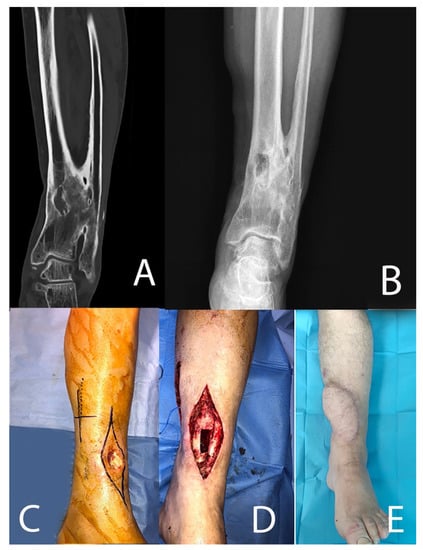

| 7 | 64, F | 3 | Yes | 5 | Yes | Type 3 | Type 4 A |

| 7 | Resection | Yes | 60 | MR CoNS | ALT | 19 | No | ||

| 11 | 18, F | 1 | No | 1 | No | Type 2 | Type 3 A |

| 11 | Resection | No | 110 | MRSA + E. coli + E. faecium | Latissimus dorsi | 29 | No | ||